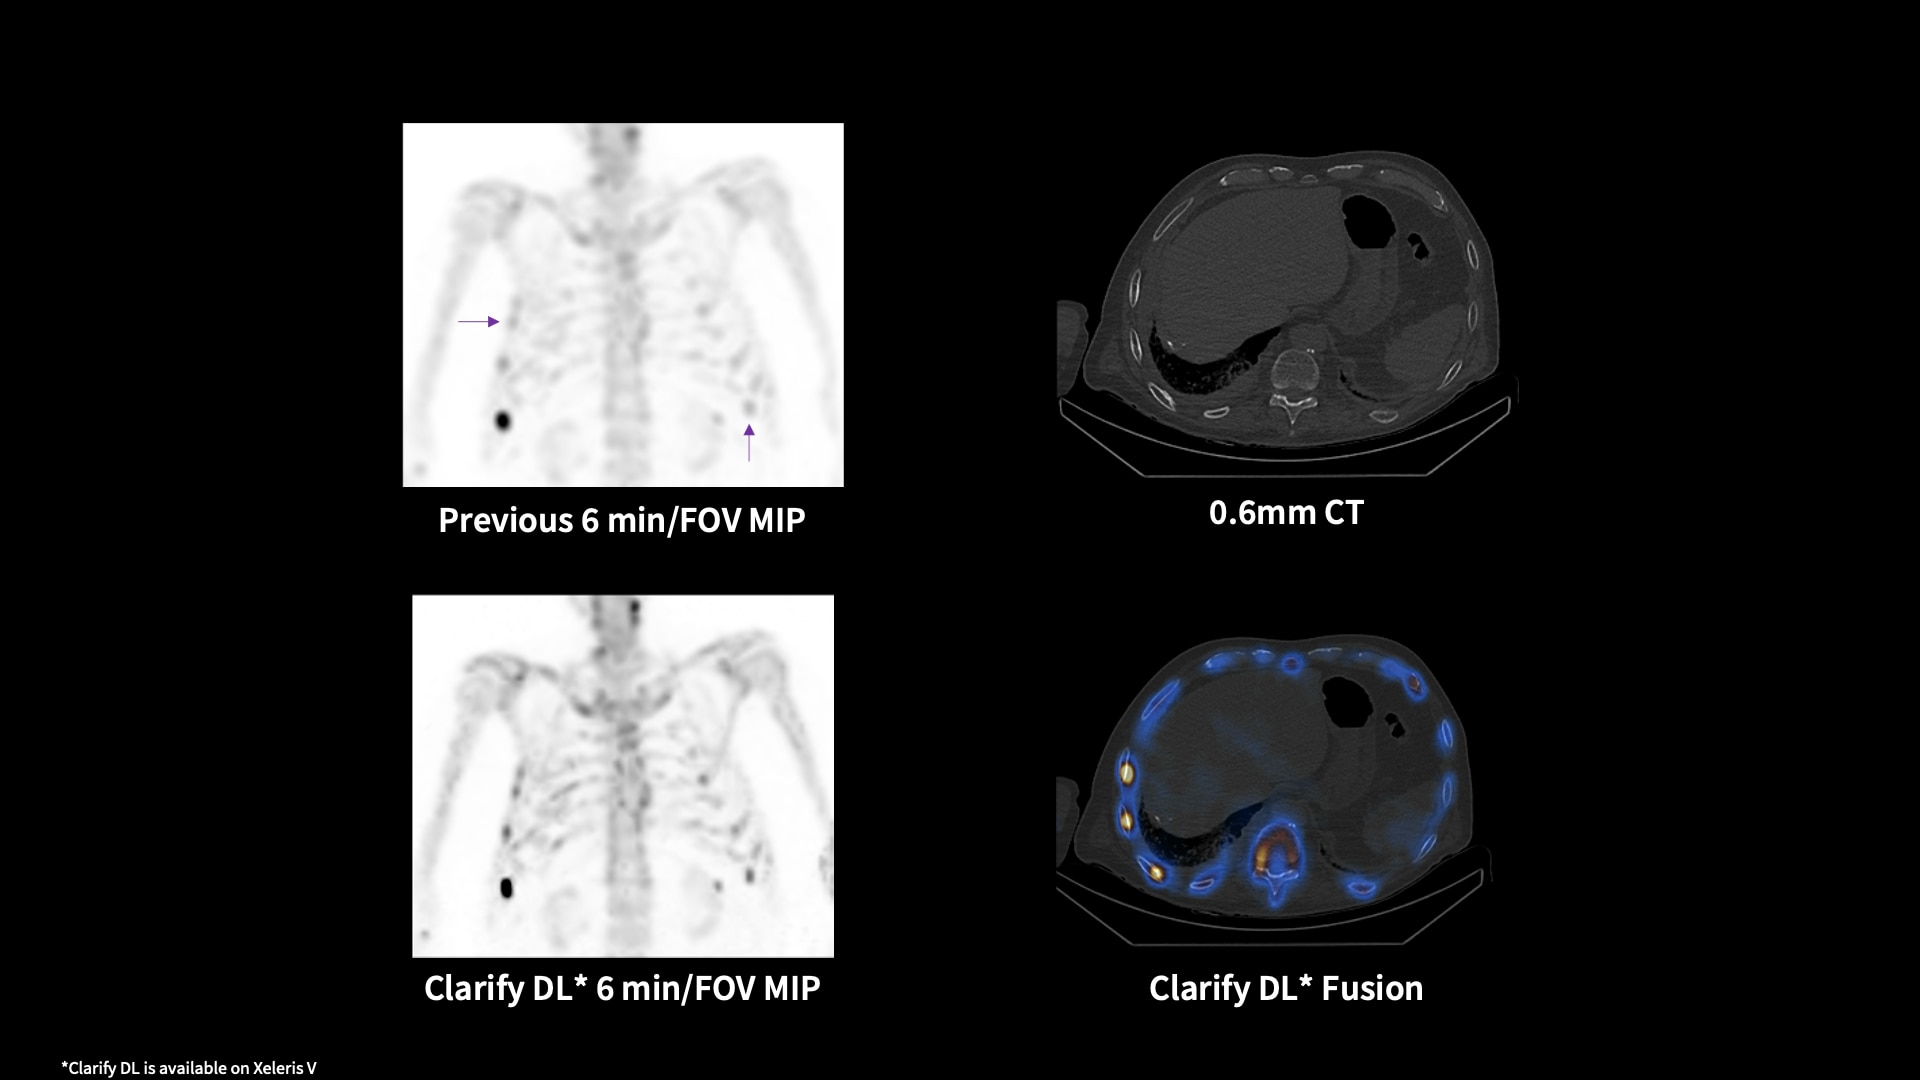

Clarify DL¹

Refocus with Clarify DL and move on from reading around the noise

Image quality has always required a trade-off between removing noise and maintaining contrast. GE HealthCare has a solution that mitigates that trade-off. Clarify DL is Aurora's AI-enabled bone SPECT image reconstruction designed to reduce noise, while retaining signal contrast. Doing so improves contrast-to-noise ratio (CNR) and contrast recovery coefficients (CRC)⁴, which are important factors in lesion detectability. With or without CT, Clarify DL is designed to achieve a new level of image quality performance without having to increase injected dose or scan time. Improved image quality performance may help increase diagnostic confidence.⁵ Clarify DL’s image resolution has been rated as better in 98% of exams.⁶

1. Clarify DL is available on Xeleris V

4. Clarify DL improves contrast recovery coefficient (CRC) up to 82% and contrast to noise ratio (CNR) up to 58% as compared to use of GE bone SPECT factory reconstruction presets for dual head cameras.* CRC and CNR are important factors in lesion detectability. *CRC and CNR demonstrated using digital phantom with inserted lesions of known size, location, and contrast, for AC and NC images.

5. Clarify DL improves dual head cameras’ image quality performance measured by Structures Similarity (SSIM) – up to 8% improvement, Mean Squared Error (MSE) up to 76% improvement, and Peak Signal-to-Noise Ratio (PSNR) - up to 18% improvement, as compared to GE bone SPECT factory reconstruction presets*. Improved image quality performance may help increase diagnostic confidence. *Demonstrated using digital phantom simulations with inserted lesions of known size, location, and contrast, for AC and NC images.

6. In 127 exams rated by total of 9 physicians, in 98% of the exams, Clarify DL’s image resolution was rated as better than the existing factory reconstruction preset images.* *As demonstrated in clinical evaluation, where each exam was reconstructed with both Clarify DL and the existing factory reconstruction preset and evaluated by 3 of the physicians.